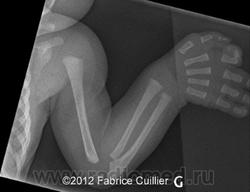

Врожденный порок развития средних отделов лица, характеризующийся плоским носом, втянутой субназальной областью (псевдопрегнией), укорочением альвеолярного отростка верхней челюсти, выпуклой верхней губой, атрофией слизистой оболочки носа без нарушения обоняния.

Рентгенологическая картина

Аплазия или гипоплазия костей носа, альвеолярного отростка верхней челюсти, лобных пазух.